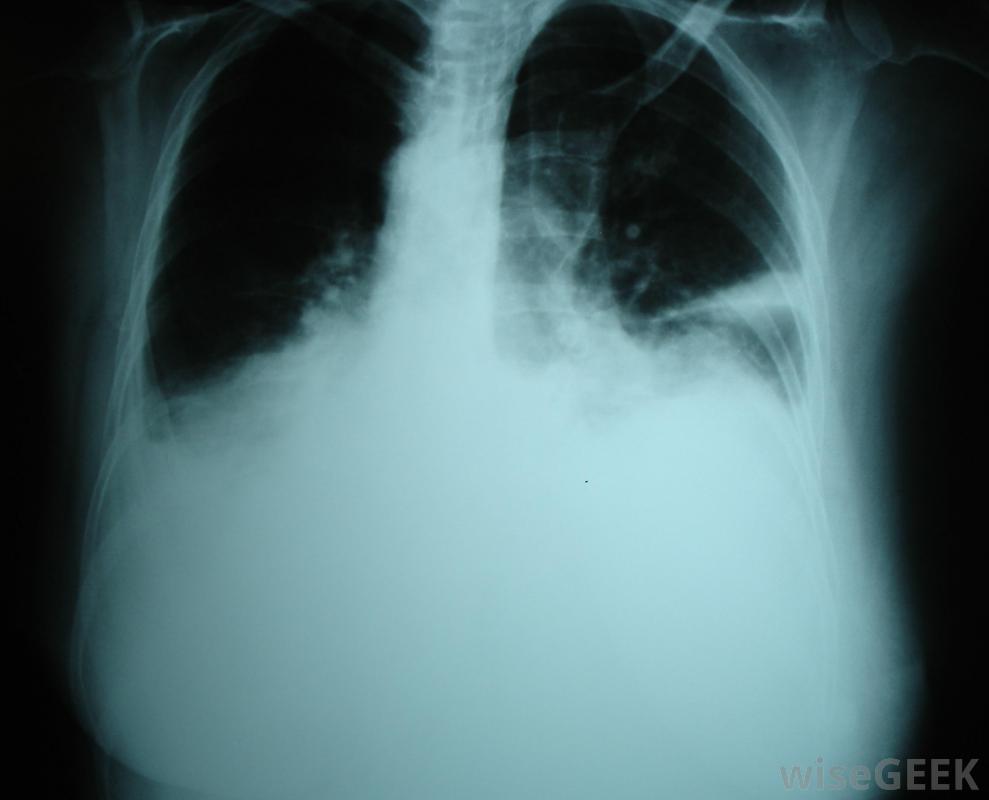

下腔静脉将缺氧的血液从下体输送到心脏。Fontan手术通常在婴儿两岁以后进行,由于高血管阻力或血液通过循环系统需要大量的工作,婴儿往往不能忍受手术。并发症可能包括感染、胸腔积液、肺部积液和心房颤动。这些并发症可能需要短期或长期用药,胸导管和外科手术。在某些情况下,Fontan手术可能不能充分改善患者的健康和生活质量,患者可能需要心脏移植。然而,对于许多患者来说,手术可以使孩子正常发育并过上正常、健康的生活